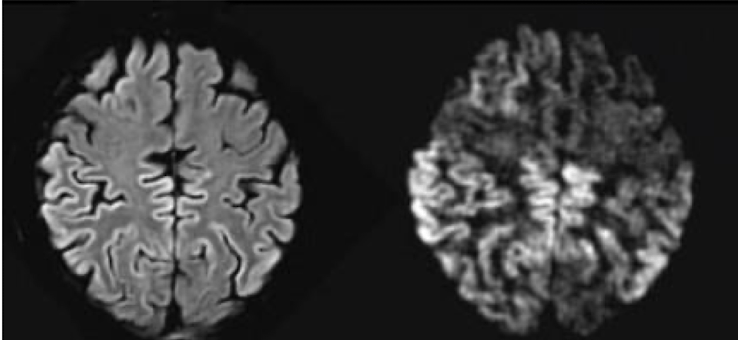

Lecanemab, an anti-Aβ antibody, can remove Aβ plaques from the brain, however, it is contraindicated in many patients due to this specific AE

ARIA => amyloid related imaging abnormalities (edema , hemorrhage)